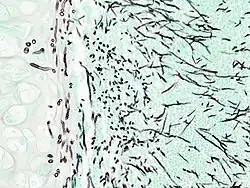

On microscopy, Aspergillus species are reliably demonstrated by silver stains, e.g., Gridley stain or Gomori methenamine-silver.[27] These give the fungal walls a gray-black colour. The hyphae of Aspergillus species range in diameter from 2.5 to 4.5 μm. They have septate hyphae,[28] but these are not always apparent, and in such cases they may be mistaken for Zygomycota.[27] Aspergillus hyphae tend to have dichotomous branching that is progressive and primarily at acute angles of around 45°.[27]